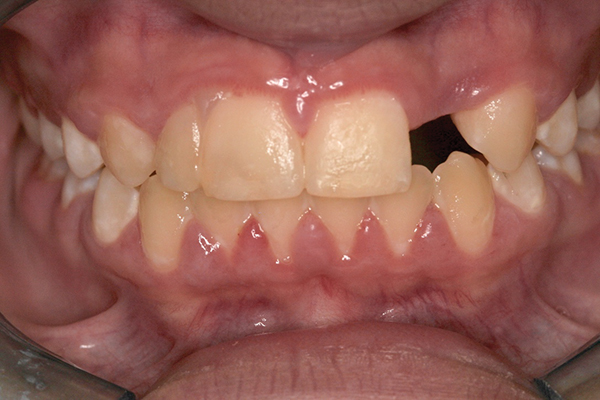

Fig 1 and Fig 2. Pretreatment photographs. Patient at 9 years of age on presentation.

A 9-year-old girl, referred to a prosthodontic office by her pediatric dentist, presented with her mother’s chief complaint: “The kids are teasing her about her big front tooth.” Findings from radiographic and clinical examinations revealed fused maxillary central-peg lateral incisors, teeth Nos. 7 and 8, and a congenitally missing lateral incisor, tooth No. 10 (Figure 1 through Figure 3). An implant was selected as the ideal treatment to replace tooth No. 10 when somatic growth was complete. A diagnostic wax-up was fabricated to determine if the fused tooth could be made to resemble two teeth, using pink composite to give the illusion of an interproximal papilla. The patient was referred for an orthodontic consultation to plan for closure of the diastema between teeth Nos. 8 and 9 and achievement of proper alignment for implant No. 10. The patient was also referred to a periodontist for pretreatment assessment of the tooth No. 10 site. An endodontist was consulted should exposure of the large pulp occur during tooth preparation.